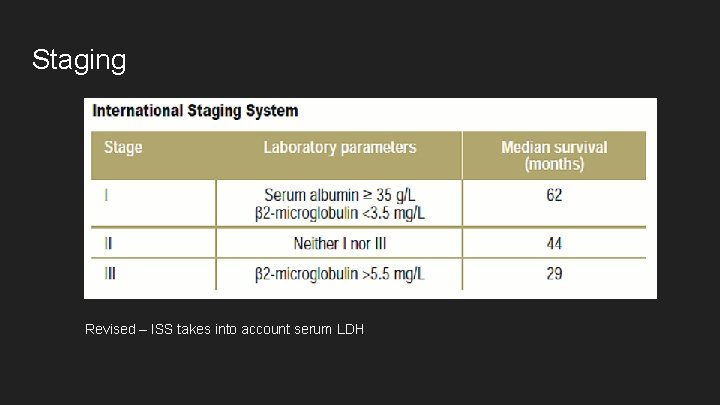

Staging Revised – ISS takes into account serum LDH